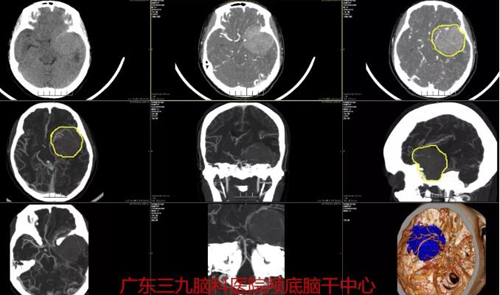

蝶骨嵴脑膜瘤是颅内常见的肿瘤,占颅内脑膜瘤的12%左右。蝶骨嵴脑膜瘤是起源于蝶骨大、小翼上的脑膜瘤,内起自前床突外抵翼点,可以分为蝶骨嵴外侧部(大翼部)、中部(小翼部)和内侧部(床突部)3个亚型。手术切除为主要治疗方法。近日,广东三九脑科医院神经外一科接诊一例蝶骨嵴脑膜瘤患者,手术切除肿瘤后患者症状缓解明显,没有其他不适。

38岁的黄女士出现间断性头痛2个月,到当地医院就诊,经头部检查发现颅内肿块,建议到上级医院诊治,遂转到广东三九脑科医院神经外一科就诊。医生详细检查后发现,患者左侧中颅窝底占位性病变,大小约4.7×5.1×4.6cm,脑膜瘤可能。患者头痛是因肿瘤压迫所致,手术切除是最有效的治疗手段。经周密安排,由张良主任主刀行“左侧蝶骨嵴脑膜瘤切除术”,术程顺利,病理报告示:非典型脑膜瘤,WHOⅡ级。

图1:术前CT及CTA结果示左侧中颅窝底占位性病变,大小约4.7×5.1×4.6cm,血供极其丰富,邻近左侧颈内动脉及左侧大脑中动脉部分被包绕,病变周围较多血管缠绕。术后CT示左侧蝶骨嵴脑膜瘤切除术后改变,原病灶已切除,术区周缘少许出血。